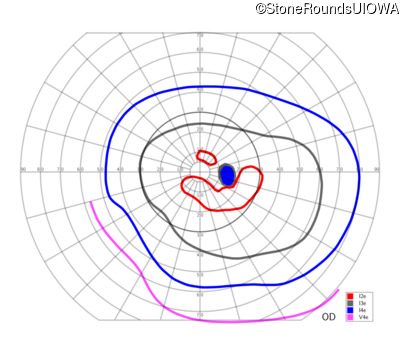

This 52 year old man had normal vision until his mid 30's when he began to have trouble distinguishing colors. the issuing 10 years he had a gradual loss of visual acuity accompanied by increasing photophobia.

| Age at visit: 55 years |

| Age at visit: 58 years |

| Age at visit: 61 years |

| Age at visit: 64 years |